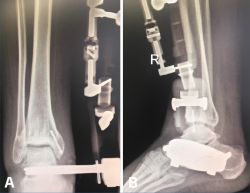

Utilizamos el fijador articulado monolateral (de tipo X-Caliber®, Orthofix). En un primer paso procedemos a colocar los pines en astrágalo y calcáneo mediante la guía radiotransparente (Figura 2), para posteriormente colocar los pines tibiales en la superficie anteromedial de la misma (a ser posible 3). Al acabar el procedimiento procedemos a realizar progresivamente una distracción de entre 7 y 8 mm (se dispone de un calibrador en el fijador que nos permite visualizar la distracción que estamos realizando) (Figura 3) bajo control radioscópico, dejando finalmente la pieza articulada totalmente libre para la movilidad tibioastragalina desde el principio. Aplicamos un vendaje compresivo de la extremidad y retiramos la isquemia (Figuras 4 y 5).

Figura 4. A y B: radiografías anteroposterior y lateral del fijador implantado con la distracción conseguida a nivel articular.